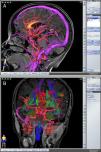

Describir la utilidad de la neuronavegación preoperatoria 3D asistida por ordenador para la localización estereoscópica de los senos venosos, ramas arteriales y cuerpo calloso, para extrapolar las referencias anatómicas sobre el campo quirúrgico y tomar decisiones antes de la intervención.

To describe the usefulness of 3D computer-assisted preoperative neuronavigation for stereoscopic location of the venous sinuses, arterial branches, and corpus callosum, to extrapolate anatomical landmarks on the surgical field and make decisions before the intervention.